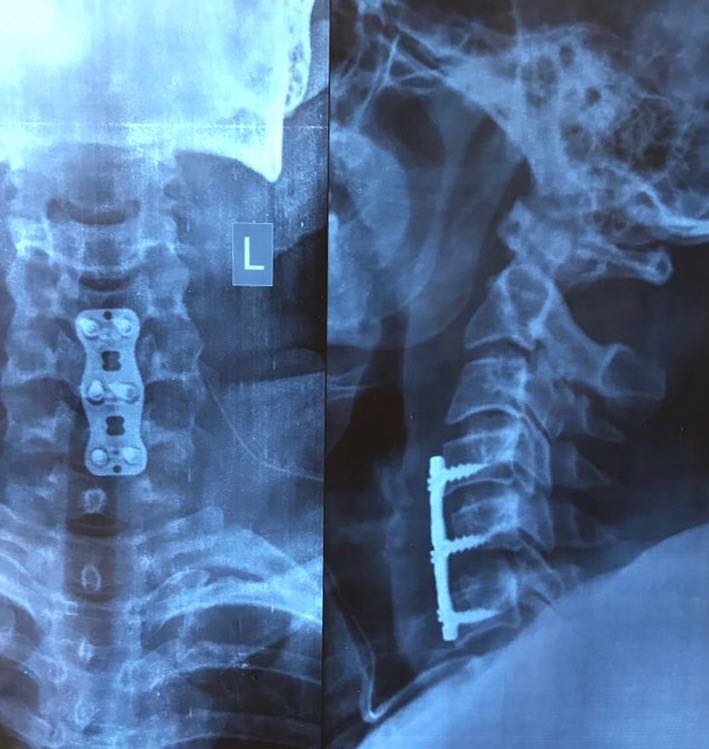

After the disc is removed, the space between the bony vertebrae is empty. To prevent the vertebrae from collapsing and rubbing together, a spacer bone graft is inserted to fill the open disc space. The graft serves as a bridge between the two vertebrae to create a spinal fusion. The bone graft and vertebrae are fixed in place with metal plates and screws. Following surgery the body begins its natural healing process and new bone cells grow around the graft. After 3 to 6 months, the bone graft should join the two vertebrae and form one solid piece of bone. The instrumentation and fusion work together, similar to reinforced concrete.